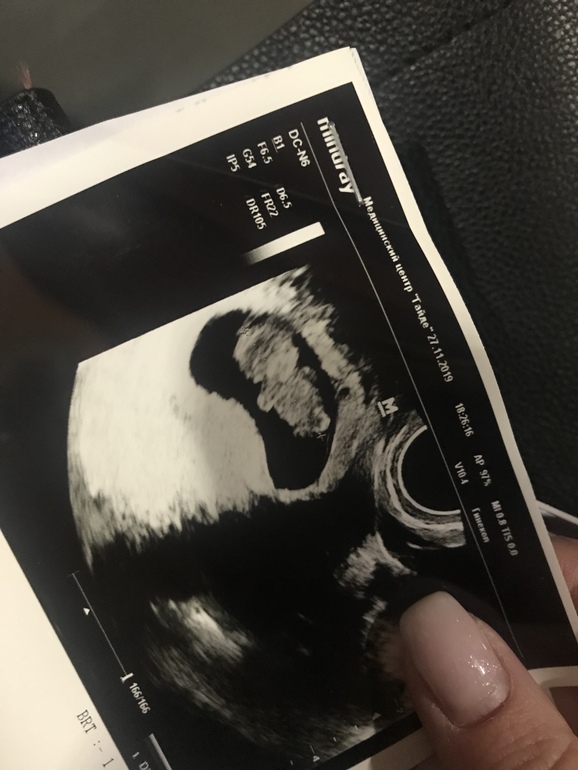

Потом мы, значит, проснулись и повернули голову в бок 😄👇

Гиня сказала - какой толстенький мишка Гамми 🐻😃

В общем, всё у нас хорошо 👌🏻 по всем показателям и нормам 🙏